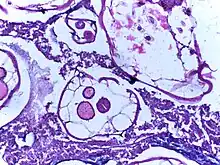

Ascaris infection: Antimesenteric splitting of the outer layers of the bowel wall due to a large amount of ascaris (South Africa)

Mass and volume

In extreme cases of intestinal infestation, the mass and volume of the worms may cause the outer layers of the intestinal wall, such as the muscular layer, to tear. This may lead to peritonitis, volvulus, and gangrene of the intestine.[9]